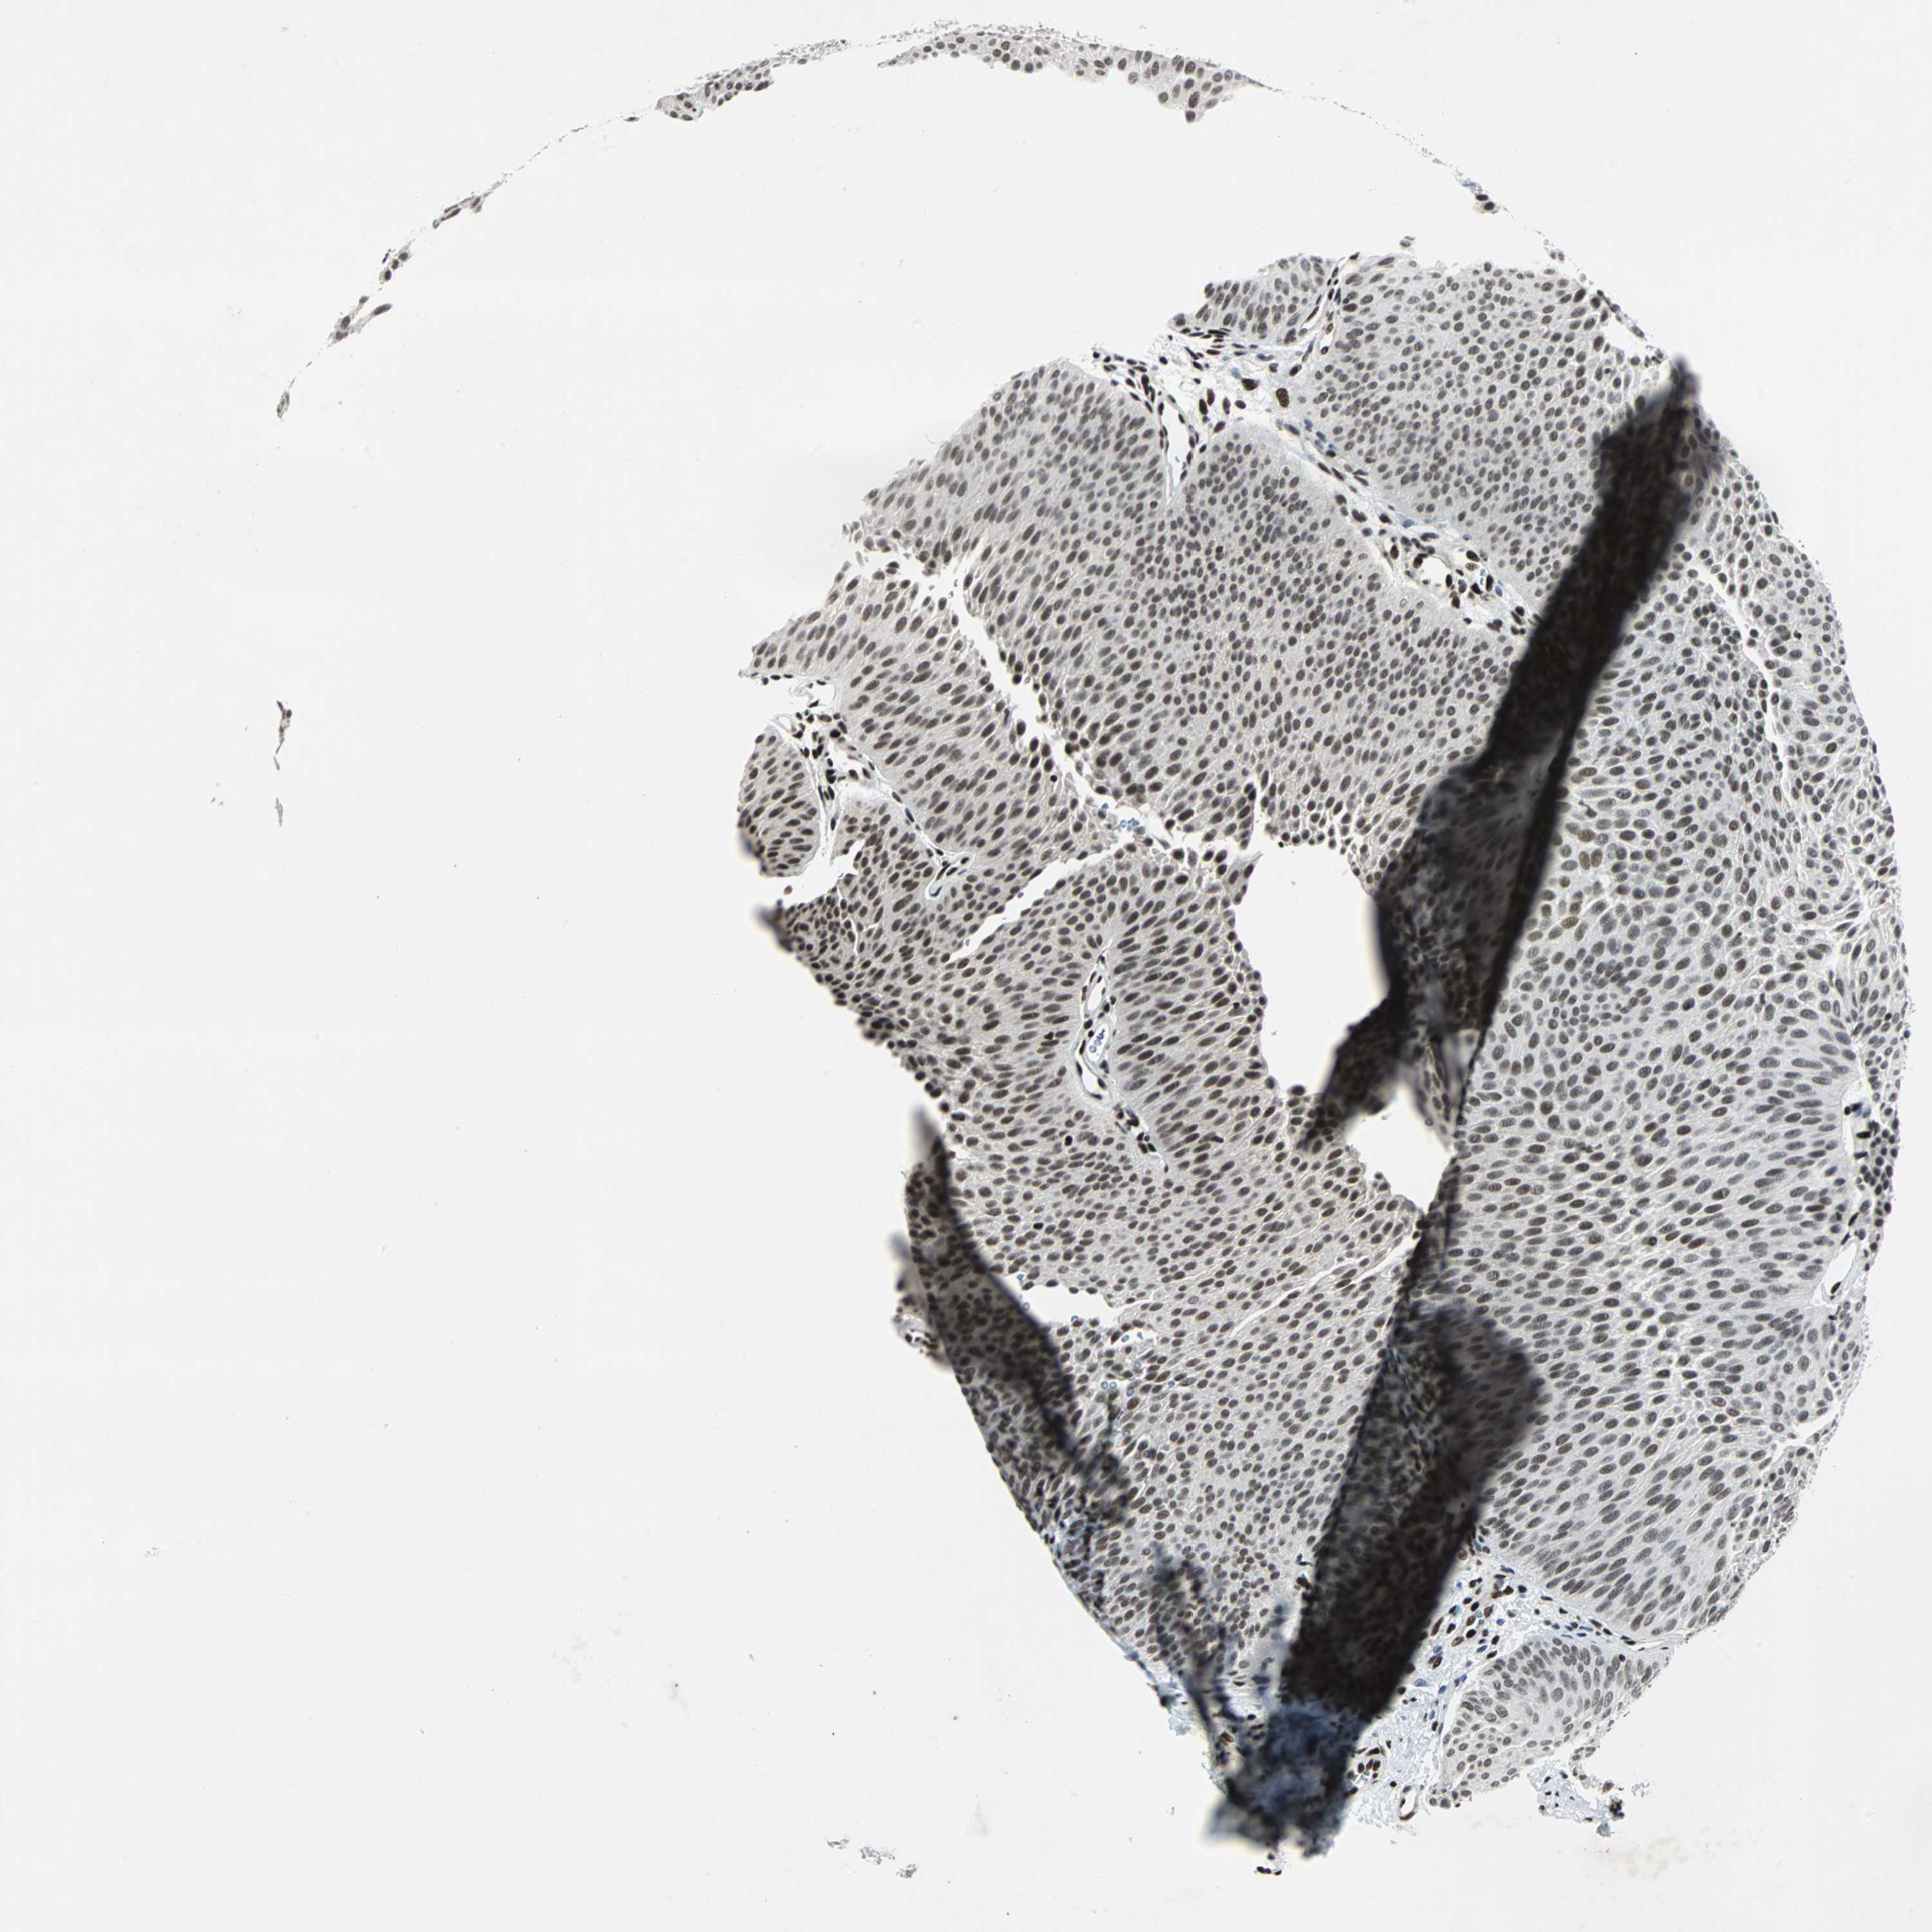

UROTHELIAL CANCER - Protein expressioni

A mouse-over function shows sample information and annotation data. Click on an image to view it in a full screen mode. Samples can be filtered based on level of antibody staining by selecting one or several of the following categories: high, medium, low and not detected. The assay and annotation is described here.

Note that samples used for immunohistochemistry by the Human Protein Atlas do not correspond to samples in the TCGA dataset.

Antibody stainingi

Antibody staining in the annotated cell types in the current human tissue is reported as not detected, low, medium, or high, based on conventional immunohistochemistry profiling in selected tissues. This score is based on the combination of the staining intensity and fraction of stained cells.

Each image is clickable and will lead to virtual microscopy that enables deeper exploration of all samples and also displays staining intensity scores, fraction scores and subcellular localization as well as patient and tissue information for each sample.

Antibody HPA004807

Antibody HPA007114

Staining

High

Medium

Low

Not detected

Intensity

Strong

Moderate

Weak

Negative

Quantity

>75%

75%-25%

<25%

None

Location

Nuclear

Cytoplasmic/membranous

Cytoplasmic/membranous,nuclear

Urothelial carcinoma, High grade

Urothelial carcinoma, Low grade